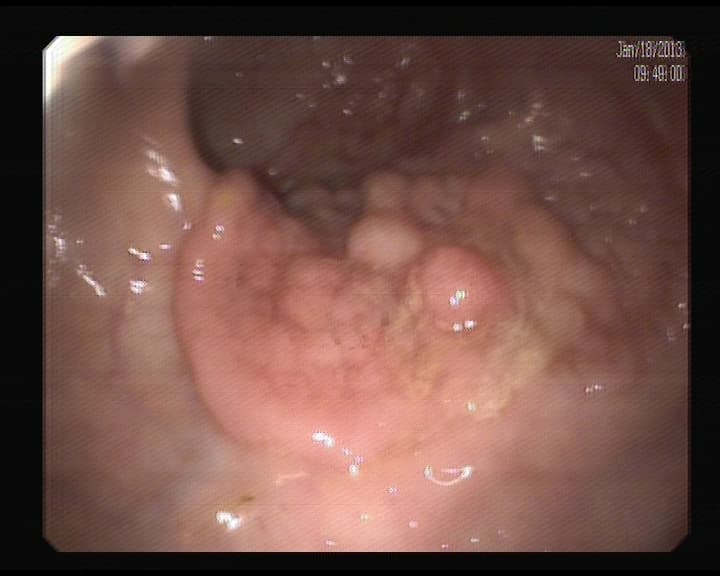

Pólipo adenomatoso, con pedículo ancho

Deben ser resecados para su analisis histólogico, y confirmar que es pólipo que se transformaría en cáncer. Esto no da sintomatología, una sangre oculta en heces, nos puede inducir a realizar colonoscopia y detectarlos.

Polipo Adenomatoso. Benigno.

Pólipo Benigno, que ha sido resecado, para evitar su transformación a cáncer.